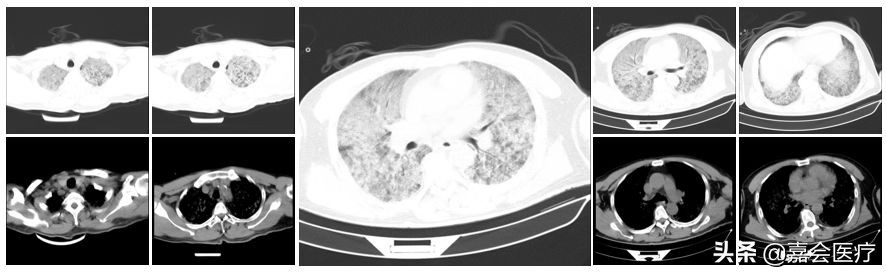

2019年9月15日出现发热伴寒战现象,体温最高达39℃,在当地予以治疗,症状未见缓解,并出现呼吸困难现象。当地医院就诊,肺部CT提示肺部出现弥漫性病变,予以气管插管机械通气治疗,但氧合难以维持。

影像检查